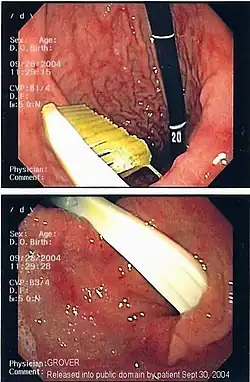

| A foreign body - in this case a swallowed toothbrush - located in the stomach cavity by using an endoscope. | |

Endoscopic foreign body retrieval is the first-line treatment for removal of a foreign body from the alimentary tract.[10]